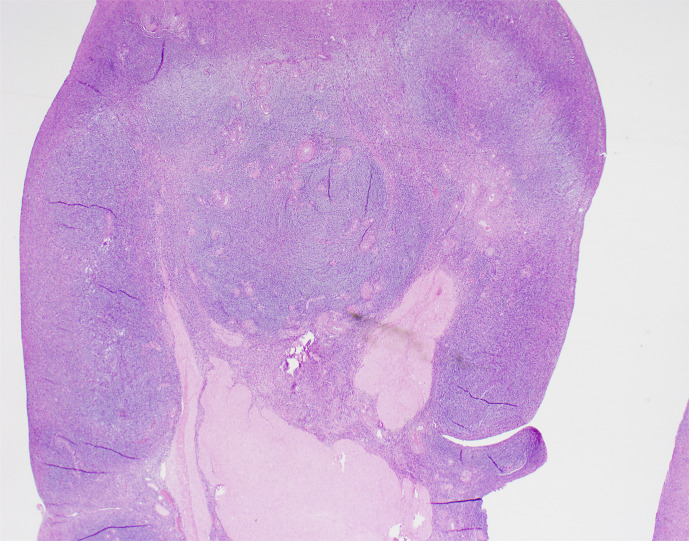

Case presentation: We present the case of a 47-year-old female with high-risk early-stage hormone receptor-positive breast cancer who despite use of GnRH agonists did not achieve an estradiol level within the postmenopausal range. She had received two different GnRH agonists (leuprolide and goserelin) and later underwent a bilateral salpingo-oophorectomy (BSO). The pathology showed stromal hyperplasia in both ovaries. After the BSO in April 2024, the GnRH agonist was stopped. The serum estradiol level remained elevated (not in the postmenopausal range) after surgery for 12 months, prior to decreasing to the postmenopausal range.

Abstract Image